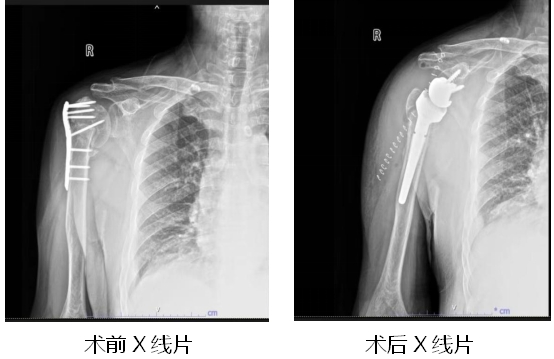

近日,一位60多岁的大爷因右肩关节疼痛,活动受限明显向91porn (湖北省中山91porn )骨外科主任王显勋求助。原来,大约一年前,大爷因外伤致右侧肱骨骨折在外院做过手术,但在恢复期间出现了关节疼痛,活动时疼痛不适。入院经检查判断大爷为“右肱骨头缺血性坏死、右肱骨骨折不连接、右肩关节粘连”。由于患者已在院外进行右侧肱骨骨折钢板内固定术,手术有一定难度,王显勋组织科内进行病例讨论,为患者制定手术方案。在做好充分的术前准备后,王显勋带领副主任黄飞、副主任医师万昌涛等骨科团队为患者行“右侧肱骨内固定装置去除术+反向全肩关节置换术”。术后,护理团队精心指导患者功能锻炼,预防其他并发症发生,患者恢复良好,对治疗效果和护理服务非常满意。

反肩置换术的全称是“反置式人工全肩关节置换术”(RTSA),是指肩关节假体的球形关节面位于肩胛骨关节盂侧,而盂杯位于肱骨近端的半限制性人工全肩关节。

反肩假体构成 反肩人工关节假体的安置